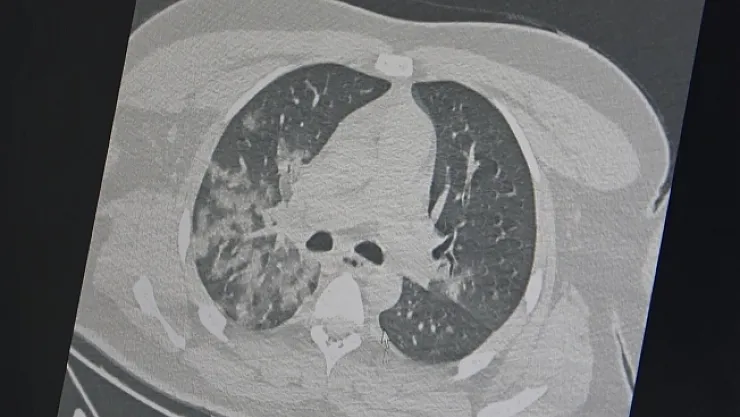

Kovid-19 salgını sonrası özellikle acil servislerde genç hastalarda ani ölümle sonuçlanan akciğer ve kalp/damar hastalıklarında ciddi artış olduğunu ifade eden Göğüs Hastalıkları Uzmanı Prof. Dr. Şevket Özkaya, açıklamalarda bulundu.

Özkaya, "Tüm dünyada en çok sorulan soru, bu artan ani ölümlerin sebebi kovid-19 aşıları mı yoksa korona virüsünün etkileri mi? Bu soru İngiltere'de 46 milyon kişi üzerinde yapılan bir araştırma ile netleşti. Kovid-19 aşılarının damar tıkanıklığı sonucu kalp krizi ve inme riskini azalttığını bildirildi. Vücudumuzda damar tıkanıklığı gelişmesinde ve akciğer, kalp ve beyin damarlarında ölümle sonuçlanan olaylara neden olan 3 temel faktör vardır. Damar iç duvarında (endotel) hasar; ameliyat, hastalık veya uzun süre seyahat sebebiyle vücudumuzun hareketsiz kalması, pıhtılaşmaya yatkınlık yapan genetik ve ilaç kullanımı (doğum kontrol hapları vb). Bu 3 faktörden en önemlisi olan damar iç duvarı (endotel) hasarı olup, kovid-19 virüsü ile enfekte olan bir kişide virüs yüküne bağlı gelişen özellikle 'sitokin' fırtınası başta olmak üzere, kan plazmasının toksik ve tahrip edici damar iç duvarında ciddi hasar yapıyor, pıhtı oluşumunun ilk aşaması gerçekleşiyor. Ayrıca hastalık veya uzun süre seyahat sebebiyle vücudumuzun hareketsiz kalması ile pıhtı oluşumuna neden oluyor ve ölümcül sonuçlar ile karşılaşıyoruz. Özellikle gençlerin kovid-19 sonrası bozulmuş damar yapısı, ağır egzersiz ve spor ile ölümcül kalp krizlerine neden oluyor" diye konuştu.